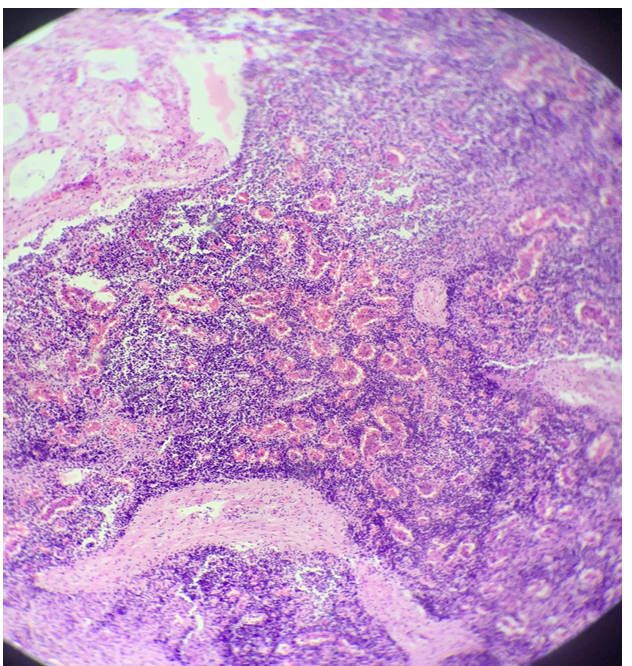

this is?

crupous (fibrinous lobar) pneumonia and chronic interstitial pneumonia

notes:

1st layer: chronic intestinal pneumonia (nederst)

2nd layer: respond to secondary infection (exudate)

3rd layer: severe accumulation neutrophils

4th layer: fibrous (upper with all the white spaces)

Bacterial origin, or fungi chyle formation, fibrin (blood protein) escapes from bv to extravascular space - formation of mass

cant see alveoli.

Nederst på bildet: fibroblasts and fibrocytes replace lung tissue. Exudation above this tissue. Line of neutrophils above exudation. Øverst: lung tissue (alveoli) with infiltration of neutrophils and exudation.